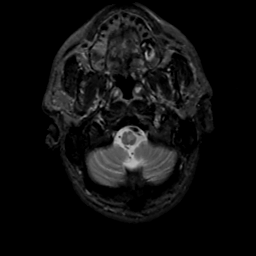

MR Study #15, June 9, 1991 -- Slice #4

[Home][Help][Clinical][Tour 1][Tour 2] Slice 4